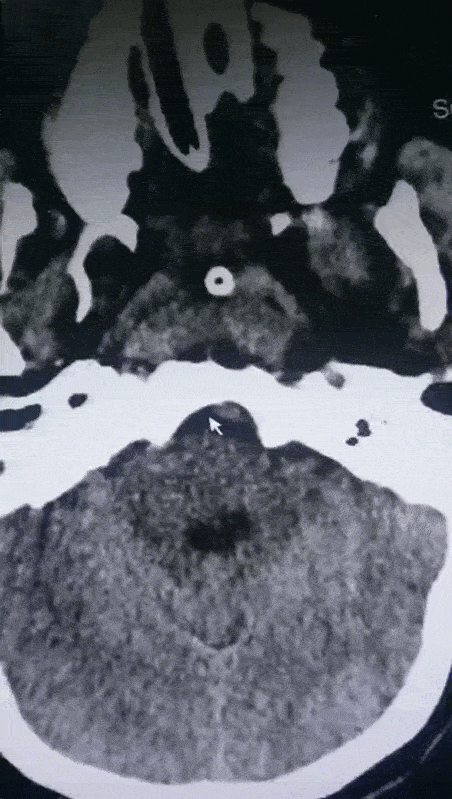

第二次CT复查出血量增加 【右】

保守治疗2天后,病情加重,瞳孔进一步扩大,出血量增加

出血部位波及到桥脑、延髓,量约有5ml,生命体征开始出现不稳定